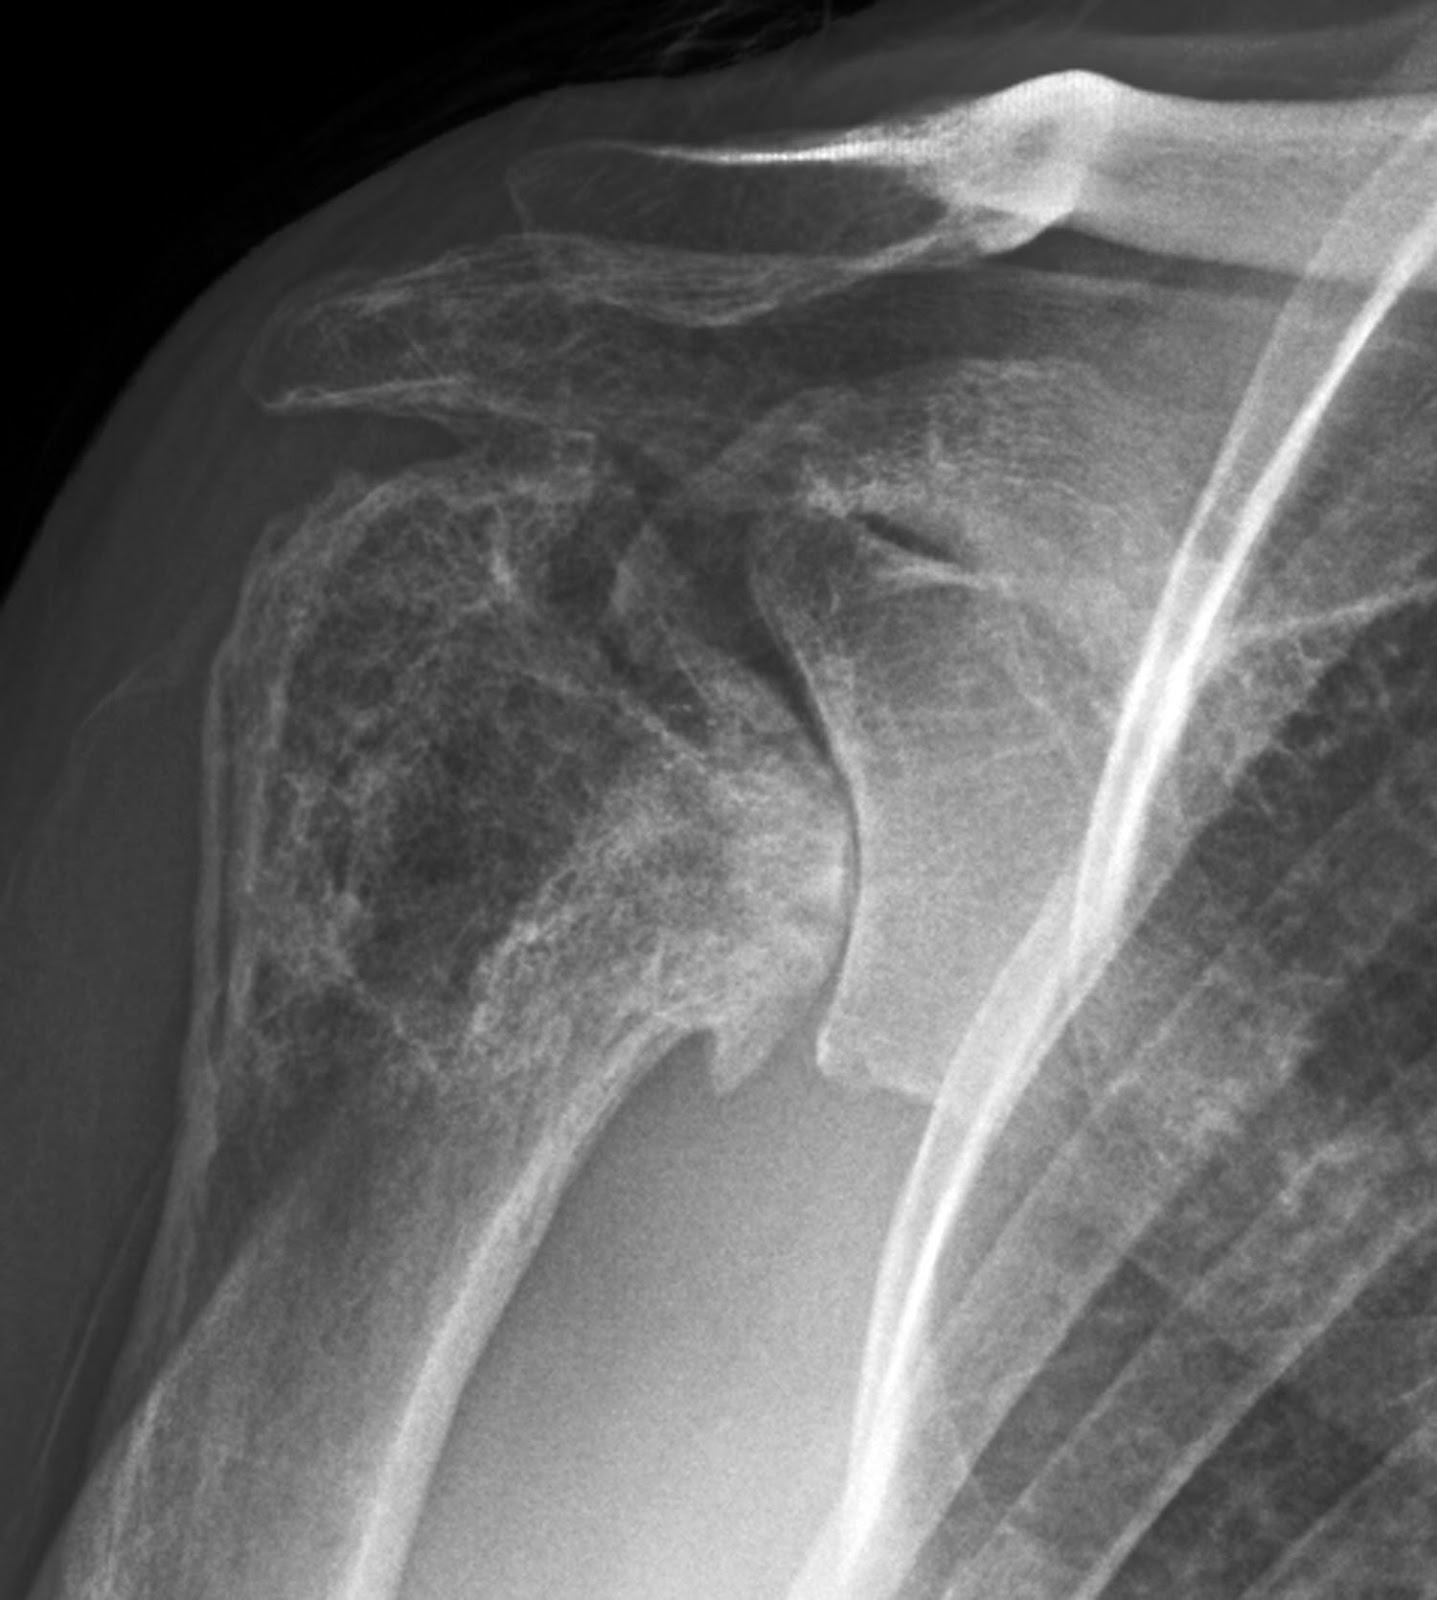

Cuff tear arthropathy is a compound degenerative condition of the shoulder that involves tendon, cartilage, and bone. In this condition chronic, massive rotator cuff defects are associated with loss of the humeral articular cartilage and superior displacement of the humeral head so that it articulates with the undersurface of the coracoacromial arch We say that the humeral head becomes “femoralized” by rounding off of the tuberosities while the coracoacromial arch and upper glenoid fossa become “acetabularized” when the humerus sculpts a concentric concavity from these structures.

In cuff tear arthropathy, the glenohumeral joint is deprived of several of its major stabilizing factors: the normal cuff muscle force vector compressing the humeral head into the glenoid; the superior lip of the glenoid concavity, which is typically worn away by chronic superior subluxation and the cuff tendon that is normally interposed between the humeral head and the coracoacromial arch. The superior displacement of humeral head slackens the deltoid so that its ability to flex or abduct the shoulder is weakened. With progression of the condition, the coracoacromial arch may become compromised, allowing anterior superior escape. Previous acromioplasty and section of the coracoacromial ligament further compromise glenohumeral stability and contribute to anterosuperior escape. The consequences of loss of integrity of the coracoacromial arch remind us of the need to preserve the integrity of the acromion and coracoacromial ligament in all shoulder procedures.